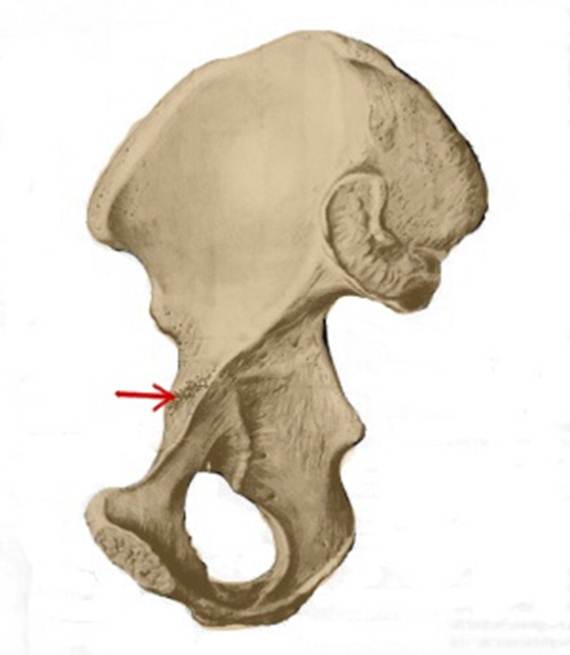

S: Стрелка указывает на tuberculum pubicum

S: Стрелка указывает на eminentia iliopubica

I:S: Стрелка указывает на spina iliaca anterior superior

S: Стрелка указывает на sulcus obturatorius (латинский язык).